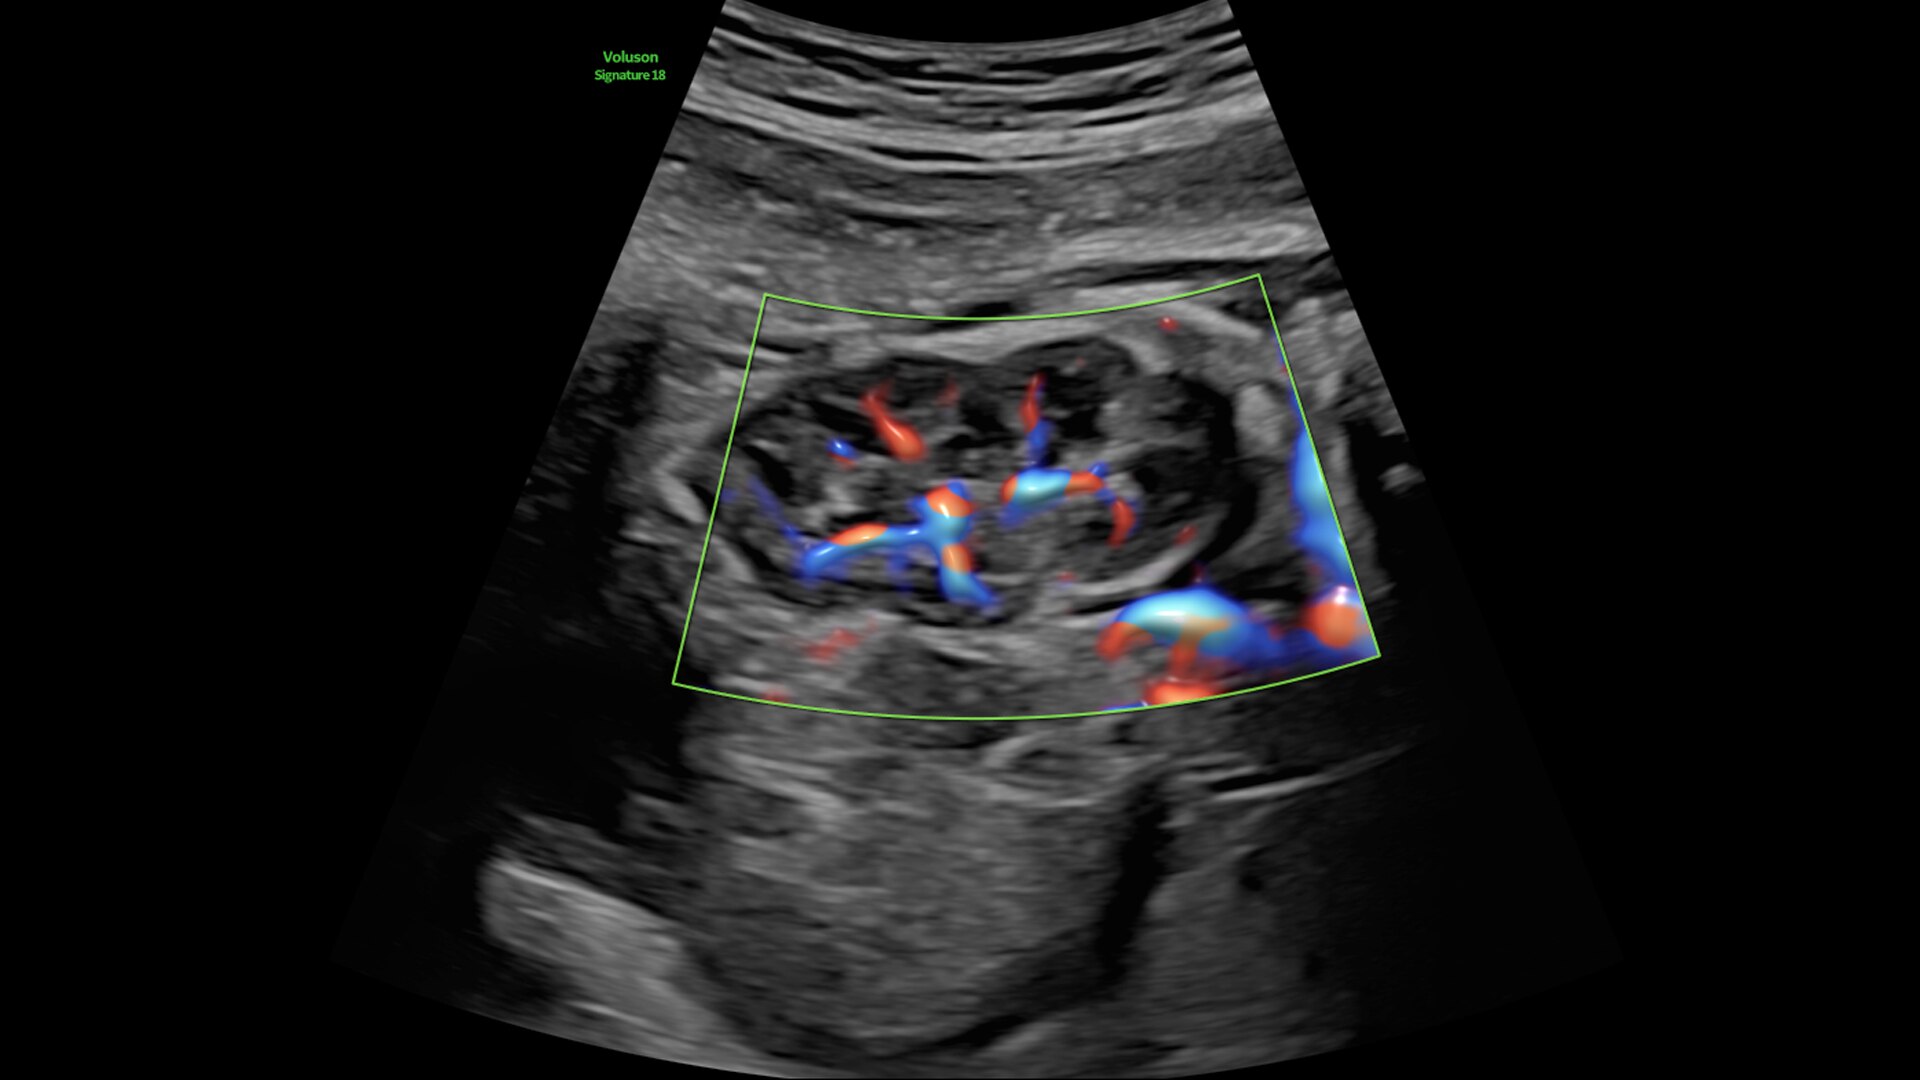

Radiantflow

Fast, easy 3D-like blood flow visualization

Next level color Doppler delivers exceptional sensitivity for easy, fast visualization of blood flow, revealing even the tiniest vessels.